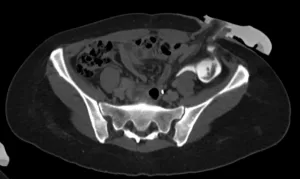

Imagens-chave

Derivação urinária em alça delgada na fossa ilíaca à esquerda. Houve boa distensão da alça de derivação, porém nota-se falha de enchimento de aspecto polipoide na fase excretora medindo cerca de 2,2 x 1,0 cm. Sugere-se prosseguir investigação.

Bricker ileal

Procedimento mais utilizado (1950) Técnica com menor complexidade cirúrgica 15-20 cm do íleo (15-20 cm da valvula ileocecal) Morbidade: 18-66% Complicações: precoces x tardias